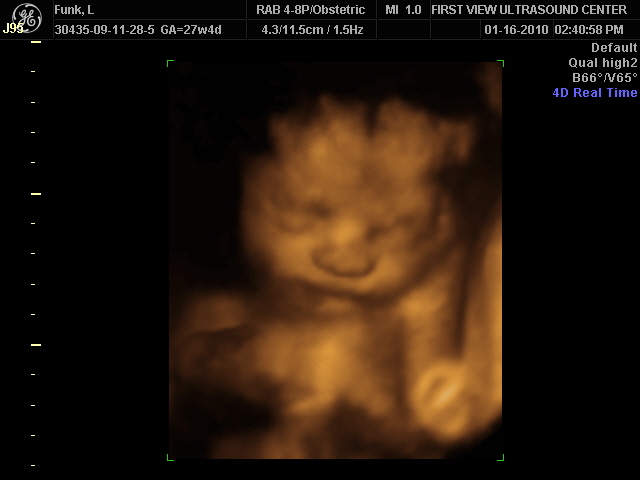

I spent the last trimester nesting. My sister and I put the finishing touches on the nursery, I cleaned all the time, I went to birthing classes with Jason and toured the hospital. I read as many books on babies as I could manage too and I tried to spend as much time with friends as I could; for I knew those times would be few and far between when baby got here. I also got my 2nd 3D ultrasound. We invited my family and Jason’s family and boy o’ boy was it so cool!

Eyan 27 weeks 4 Days gestation